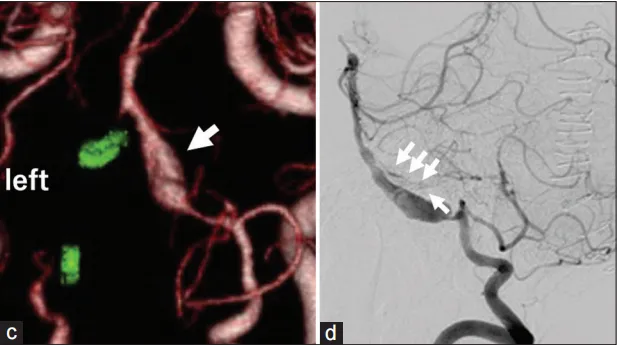

然而,术后第11天,随访CTA显示对侧VADA无症状扩大(图3c-d)。教授通过外侧枕下入路近端夹断右侧VADA(图4)。同时,通过颞下入路进行颞浅动脉-小脑上动脉旁路术,以保持后循环中的脑血流(图5)。术后双侧VADA被切除,康复后约1个月出院且术后1年随访期间病情平稳。

图3c-d:(c)术后第11天CTA显示右侧VADA迅速增大(箭头);(d)右侧椎血管造影侧视图显示右侧VADA远端延髓动脉穿孔(箭头)和大脑后动脉的前交通段发育不良。

图4a:右侧颞浅动脉-小脑上动脉(SCA)旁路和右侧椎体夹层动脉瘤近端夹闭的皮肤切口线。

图5:CTA显示双侧椎体夹层动脉瘤闭塞,颞浅动脉-小脑上动脉搭桥术未闭(箭头)。